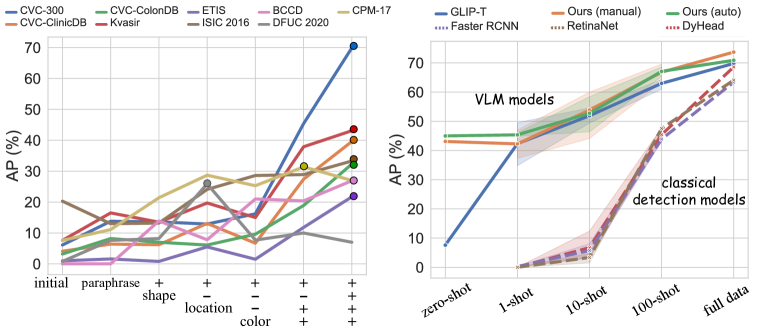

Transfer performance surpassing supervised methods To prove that text prompts are effective for cross-domain transfer, we conduct extensive experiments under both zero-shot domain transfer and supervised transfer (fine-tuning) settings. We include a series of supervised baselines: FasterRCNN, RetinaNet, and DyHead-L for comparisons. As illustrated in Figure 2, our full data fine-tuned models with well-designed medical prompts (dark blue) surpass the supervised baseline (e.g., DyHead-L in the figure) by a large margin across all datasets. Moreover, even zero-shot (brown) or 100-shot (sky blue) results on some datasets, e.g., CVC-300 and Luna-16, can rival the full data fine-tuned supervised models. The quantitative numbers are respectively shown in Table 2 for non-radiology datasets, Table 3 for polyp datasets, and Table 5 for radiology datasets. This is also supported by Figure 3 (right) where the VLMs significantly outperform the classical detection models with fully supervised learning, especially in few-shot settings.

The effectiveness of attribution injection and auto-prompts In section 3.2, we discussed that adding attributes could make the models perform better in zero-shot tasks. Here, we demonstrate in Figure 3 (left) an overall pattern of the effect of attribute injection on performance under the zero-shot setting. As shown in the figure, the overall performance increases as more attributes are integrated into the prompts. This is also illustrated in Table 4 on the BCCD dataset, where various attributes and their combinations are shown to improve the results. As this process is rather tedious and time consuming, we need qualified automatic approaches to accelerate the generation process to scale up without sacrificing too much performance. Fortunately, the models with our proposed auto-prompts, especially with the hybrid and MLM-driven approaches, show comparable results to those with manually created prompts and surpass those with default prompts by a landslide. For example, the MLM-driven approach achieves an AP of 24.8% for zero-shot on the DFUC2022 dataset, while the GLIP-T baseline with default prompts only gives 0.1% for the zero-shot performance (Table 2). Figure 4 shows an example of the auto-prompt generation with the hybrid approach.